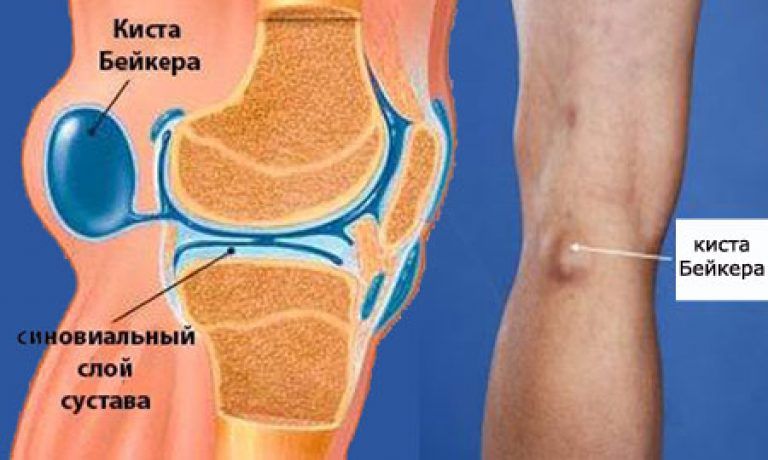

Суставная Жидкость и Головка Сустава: Обзор и Здоровье